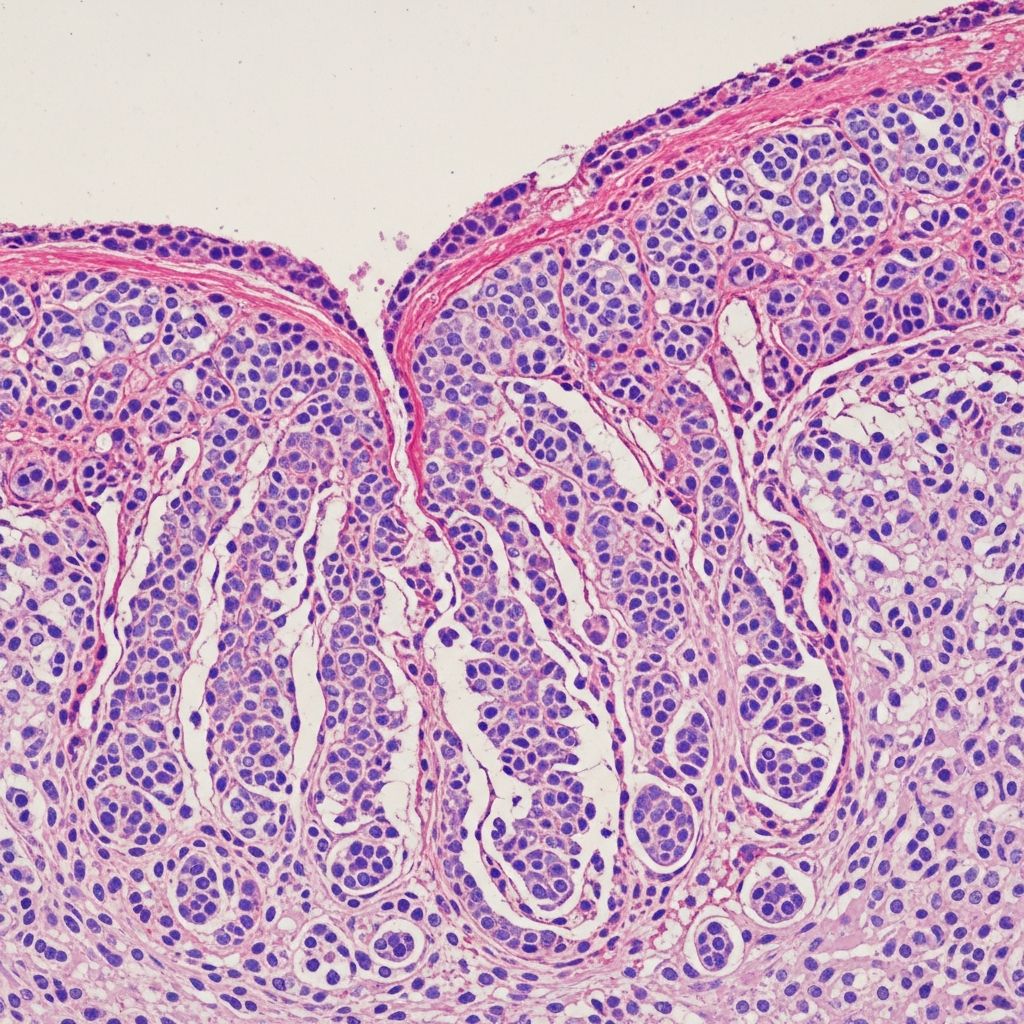

Histopathology confirms diagnosis, revealing broad, bulbous papillary projections of well-differentiated SCC extending into deep dermis. Minimal cytological atypia: large keratinocytes with abundant cytoplasm, sharp stratification, and keratin pearls filling ‘cuniculi’ burrows.

Key microscopic features:

- Exophytic growth: Pushing borders without jagged invasion.

- Keratin-filled tracts: Horizontal and vertical sinuses lined by squamous epithelium.

- Stromal inflammation: Dense lymphocytic infiltrate.

- No/ minimal atypia: Rare mitoses; low Ki-67 index.

- Bone invasion: Reactive osteoclastic activity in advanced cases.

Immunohistochemistry shows p63 positivity and low p53 expression. Biopsy must include deep burrows to avoid sampling error.